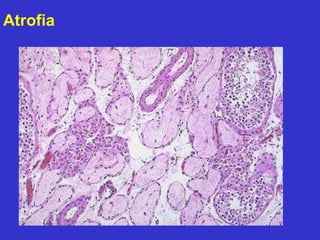

Atrofia

Testículo

normal Testículo

atrófico